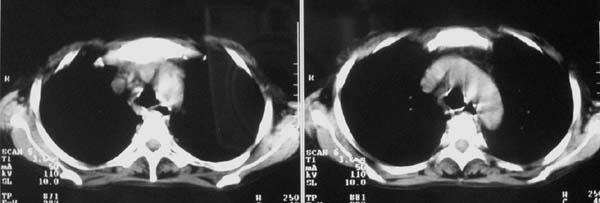

以下是引用zjzjr在2007-9-20 12:29:00的发言:[br]双肺磨玻璃改变,考虑肺水肿.

以下是引用yangzongshan在2007-9-20 18:29:00的发言:[br]两肺毛玻璃样改变,其内可见肺纹理影,无胸腔积液,故考虑肺泡蛋白沉积症

以下是引用276894491在2007-9-20 13:40:00的发言:[br]考虑肺水肿;外源性过敏性肺炎不排除。

以下是引用逸风在2007-9-20 20:45:00的发言:[br]两肺磨玻璃样改变,临床病史短,发热,考虑病毒感染合并右肺代偿性肺气肿.待排肺水肿,病史短,不支持肺泡蛋白沉着症.